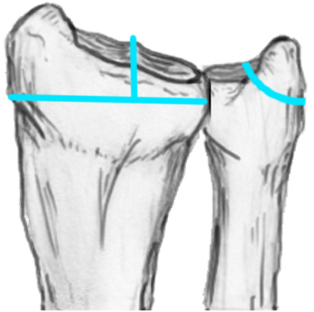

Distal Radius Angles

- radial inclination  22°

4.  Radial inclination < 15o